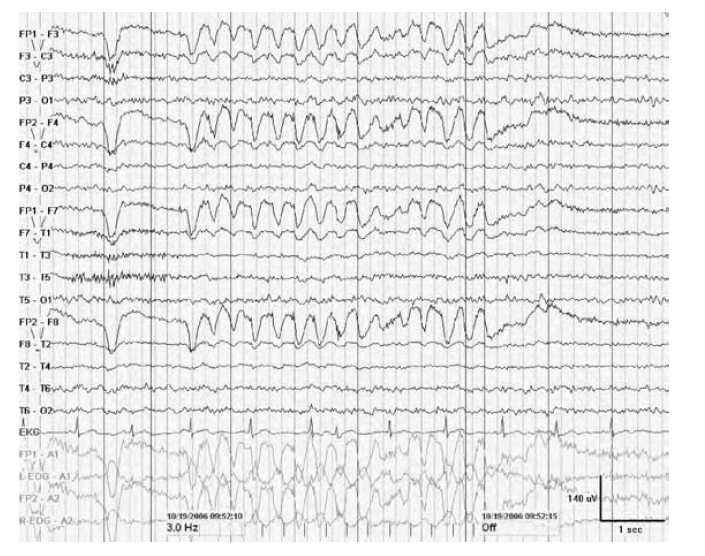

WHAT RESPONSE IS SHOWN

A photomyoclonic response during intermittent photic stimulation. Notice the spike-and-wave artifact created in the frontopolar channels.

The photomyoclonic response is an extracerebral response obtained from the frontalis muscles of the scalp. Contraction of the anterior muscles of the scalp produce EMG artifacts that vary from single to sustained myogenic potentials